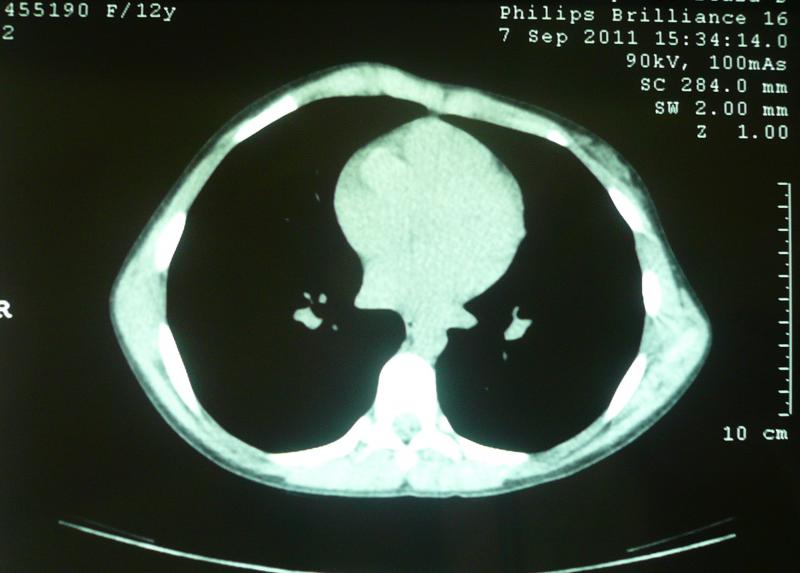

PECTUS CARINATUM CONDROMANUBRIAL

Tambien conocido como SINDROME DE CURRARINO SILVERMAN, o TIPO 2.

Se caracteriza por presentar una protursión alta a nivel del esternón, con forma de herradura.

Puede ser confundido con un tórax excavado por ojos no expertos.

Lo que tenemos es un Esternón corto y ancho, cuyos nucleos de crecimiento se osificaron y fusionaron tempranamente, dando lugar a la deformidad descrita.